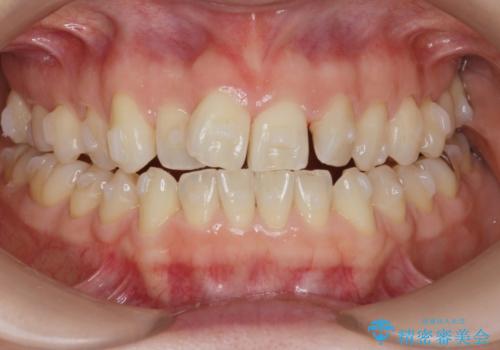

前歯の目立つガタつきをマウスピース矯正で治療

- 大きく傾いてしまった前歯のガタつきの改善を求めて来院されました。

前歯のガタつきをしっかりと取り、機能的・審美的に理想的な歯並びをマウスピース矯正で達成します。

強度のガタつきはマウスピース単体では並び切ることが難しいこともありますが、しっかりと装着していただいたことで良好な治療結果を得ることができました。